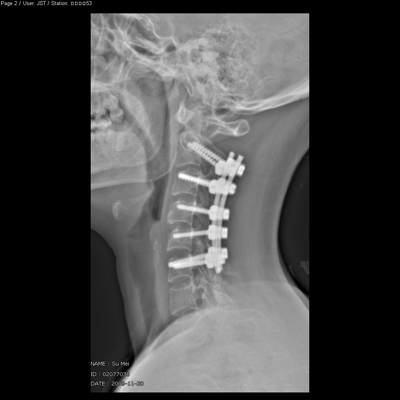

术后侧位平片